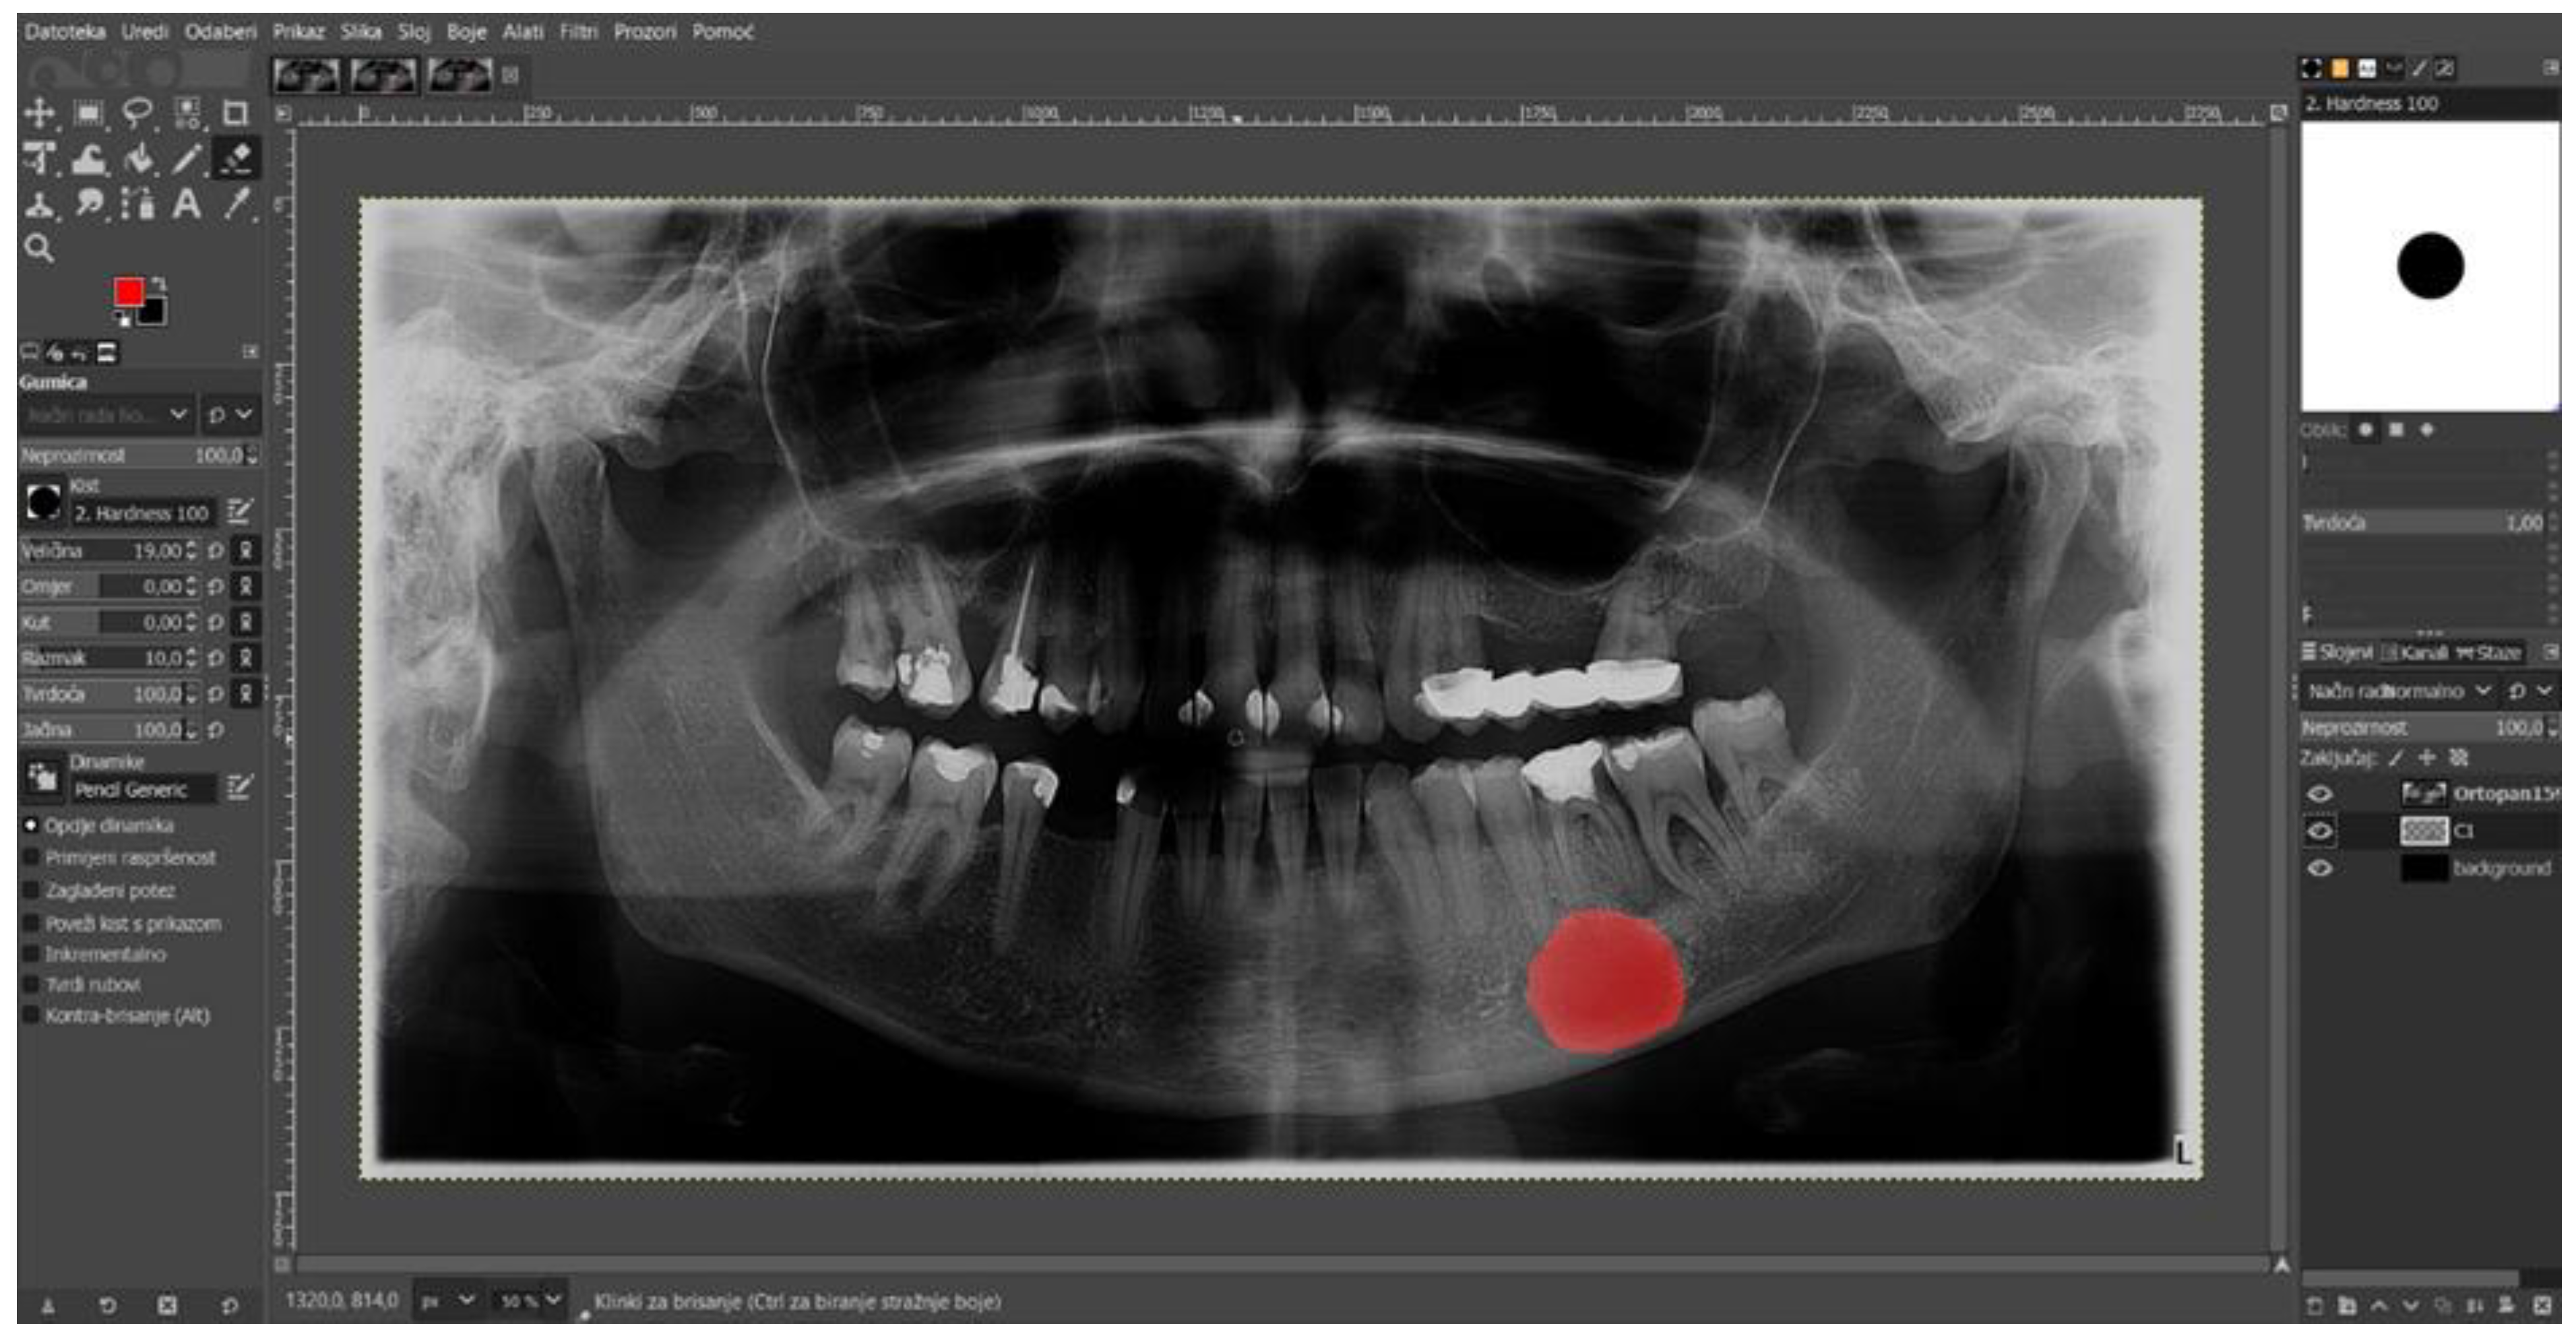

The digital panoramic radiographs were carefully retrieved from the image database and saved in the Joint Photographic Experts Group (.JPEG) format, maintaining a resolution of 2776 × 1480 pixels. To develop an AI model that can label and diagnose radicular cysts of the lower jaw, the previously saved images needed to be prepared for annotation. Preparation was carried out by an oral surgeon, a radiologist, and a maxillofacial surgeon. The process involved marking the radiolucent lesion on each image using the GIMP program (GNU Image Manipulation Program). GIMP is free and open-source image editing software available for various operating systems, including Linux, macOS, and Windows. It was developed by a volunteer team of programmers through the GNU project and offers a rich set of tools for image processing, drawing, color correction, and format conversion. One of the key features of GIMP is the ability to import and save files in different formats, meeting the needs of a large number of users, and it is also open-source software.

The previously saved images in JPEG format were imported into GIMP 2.10.32 software. The image were then converted into a semi-transparent layer by changing the opacity parameter to 60 percent. This process makes the loaded image 60 percent visible and 40 percent transparent, which facilitates easier lesion marking. To ensure precise annotation, the brush settings used to draw the lesion edges need to be adjusted. In this study, a circular-shaped brush with 100 percent hardness was used. After completing all of the previous steps, the zoom-in option was selected for the lesion, and the lesion was marked with the brush. During the marking process, errors occurred in filling the lesion with the red brush, which were corrected using the paint bucket tool. The fully marked radiolucent lesion was saved in XCF (eXperimental Computing Facility) format for further preparation for AI model development (Figure 2).

Figure 2. Manually annotated radicular cyst in the GIMP program located in the lower jaw.